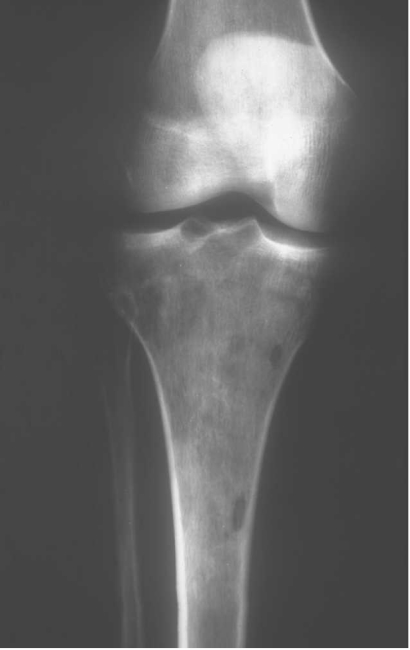

Metáfisis de huesos largos (>50% rodilla). Lesión lítica pura, agresiva (permeativa/moteada), sin matriz. Masa de partes blandas frecuente. "Secuestro óseo" sugerente.

Radiografía / TC: hallazgos clave

Patrón lítico puro y agresivo: geográfico (tipo IB/IC de Lodwick) o permeativo/motado. Ausencia de esclerosis reactiva y de matriz osteoide/cartilaginosa. Bordes mal definidos. Destrucción cortical y masa de partes blandas (80%). Signo del "secuestro óseo": fragmento de cortical o esponjosa atrapado en la masa tumoral (sugerente, no patognomónico).

| Radiografía | Lítica pura, agresiva, sin matriz. Posible fractura patológica. | Estudio inicial. Sospecha de malignidad. Guía para solicitar RM. |

| TC (sin contraste) | Detalle de destrucción cortical, "secuestro óseo", ausencia de calcificaciones. | Planificación biopsia (vía segura). Evaluar fractura. |